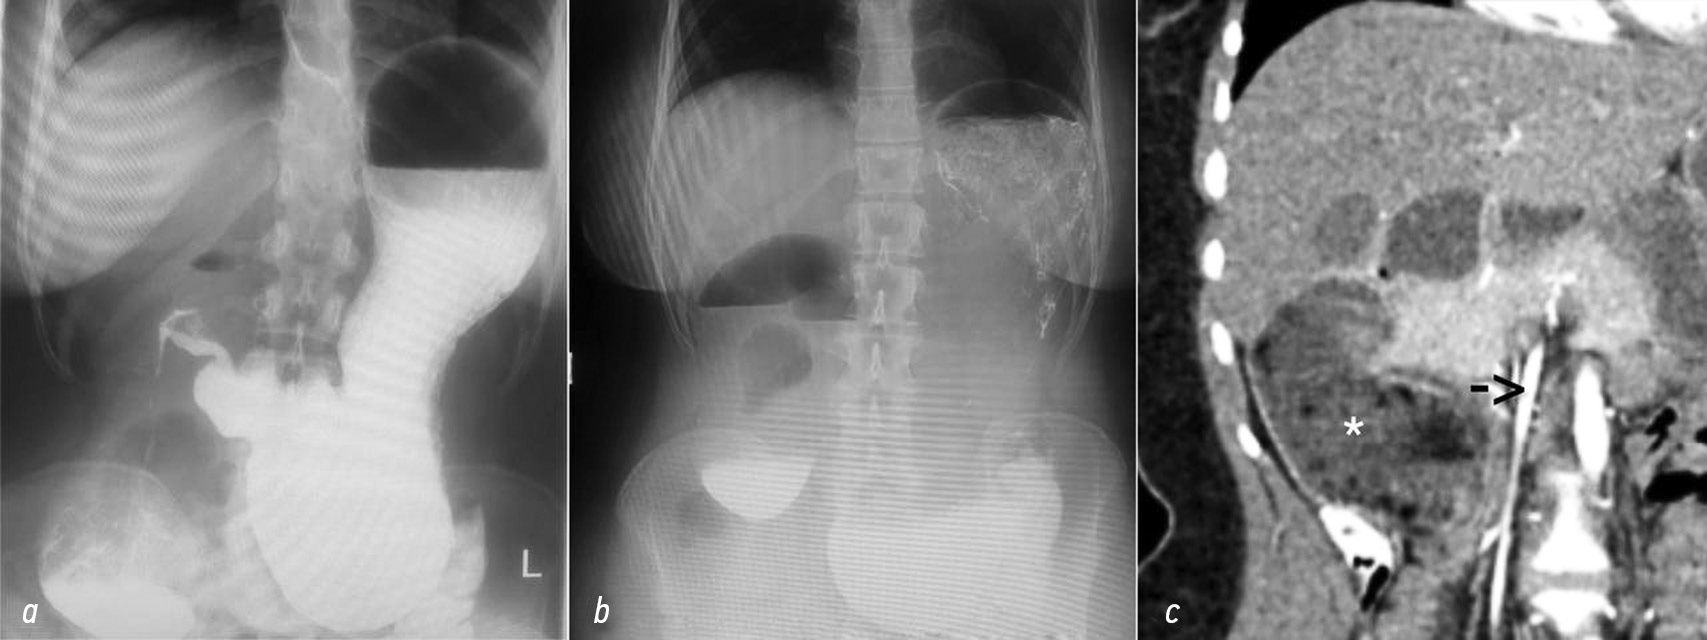

По данным рентгеноскопии желудка и ДПК с контрастированием бариевой взвесью желудок располагался полувертикально, дно его достигало входа в малый таз. Контраст болюсно поступал в дуоденум, при этом в ее вертикальной части отмечалась его задержка с формированием уровня жидкости (рис. 3, а) При проведении водно-сифонной пробы гастроэзофагеальный рефлюкс не определялся. На контрольной рентгенограмме органов брюшной полости через 1 ч после исследования пассажа контраста отмечено не было (рис. 3, с), через 3 ч — незначительное его количество определялось в петлях тонкой кишки, при этом горизонтальный уровень жидкости в проекции желудка и начальных отделах ДПК сохранялся, через 6 ч — рентгенологическая картина не имела существенной динамики.

Рис. 3. Исследования желудка и двенадцатиперстной кишки: а — рентгеноскопическое с контрастированием бариевой взвесью; b — обзорное рентгеноскопическое через 1 ч после исследования; с — компьютерная томография органов брюшной полости, отмечается резко расширенная двенадцатиперстная кишка (отмечена звездочкой) справа от верхней брыжеечной артерии (стрелка)

Fig. 3. Studies of the stomach and duodenum: a — X-ray examination with barium contrast; b — overview X-ray 1 hour after the examination; c — computerized tomography of the abdominal organs, showing a markedly dilated duodenum (*) to the right of the superior mesenteric artery (arrow)